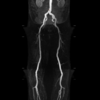

IRM CHARENTON, IRM vasculaire à Charenton-le-Pont

Qu’est-ce qu’une IRM vasculaire ?

L’IRM vasculaire est un examen qui permet d’étudier les vaisseaux au niveau artériel et/ou veineux :

• Angio-IRM cérébrale

• Angio-IRM des vaisseaux du cou

• Aorte thoracique, abdominale

• Artères rénales

• Angio-IRM des membres inférieurs